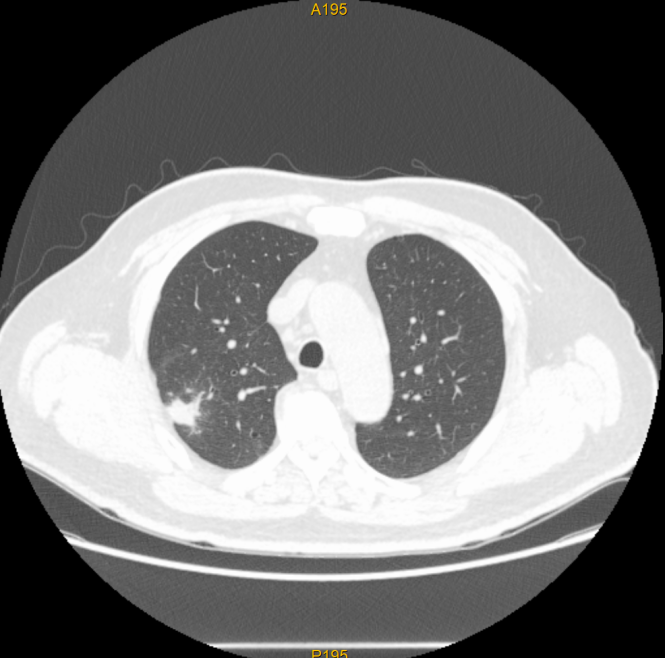

近日,我院肿瘤放射治疗科应用体部立体定向放疗(SBRT)技术,为一名胆管癌肺转移患者实施了精准放射治疗。通过制定规范的放射治疗计划,肺部两个转移病灶在接受SBRT治疗后基本消失,复查影像显示肿瘤已得到良好控制,彰显了精准放疗技术在肿瘤治疗中的独特优势。

该患者为胆管癌术后出现肺转移,两个转移病灶分别位于右肺上叶后段(大小26*25mm)及右肺下叶前基底段(大小28*30mm)。此前,患者已接受肝动脉化疗灌注(HACI)及多疗程全身化疗,但肺部病灶仍有增大趋势,治疗一度陷入困境。

治疗过程非常顺利,患者无明显不适。治疗结束后复查,两个肺部转移病灶已基本消失,显示出SBRT在局部肿瘤控制方面的绝对优势。这一结果不仅为患者带来了新的希望,也再次印证了精准放疗在肿瘤综合治疗中的重要地位。